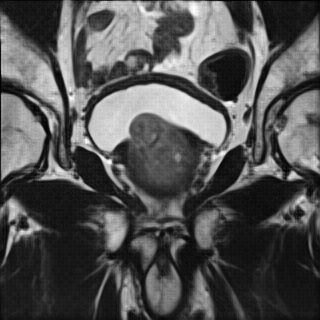

Refer to caption

(a) LR input to SRGAN 8x

(b) SRGAN 8x

Figure 5: SRGAN result for 8×8\times upscaling compared to LR input

Fig. 4 contains an example SR output for each method and the LR and HR images for reference. The LR image is severely pixelated and has no edge fidelity. While the image produced via bicubic interpolation has no pixelation, this method is still unable to preserve the high frequency information found in the ground truth image. The Sparse Representation method produces slightly better results than the previously discussed methods. However, the large amount of space and time overhead required by this model precludes it from clinical use. The SRCNN begins to show edge preservation, however the features within different regions of the output SR image are smoothed out. The SRCNN is especially biased toward smoothing the image because the network only uses MSE loss. The SRResNet has both MSE and perceptual loss yet fails to outperform the SRGAN. Clearly, the discriminator network seeks out the high frequency information that differentiates HR and LR images, thus forcing the SRGAN output to have far more high frequency details than the output of the SRResNet. The SRGAN 8x network is not able to maintain as high an edge fidelity as the SRGAN 4x network. This result is expected because the SRGAN 8x network is provided with far less information since the input LR image is a further 2x smaller in both dimensions (Fig. 5). Overall, in comparing the SRGAN to the other models, the outputs from the SRGAN are visually closer to the original HR ground truth images.